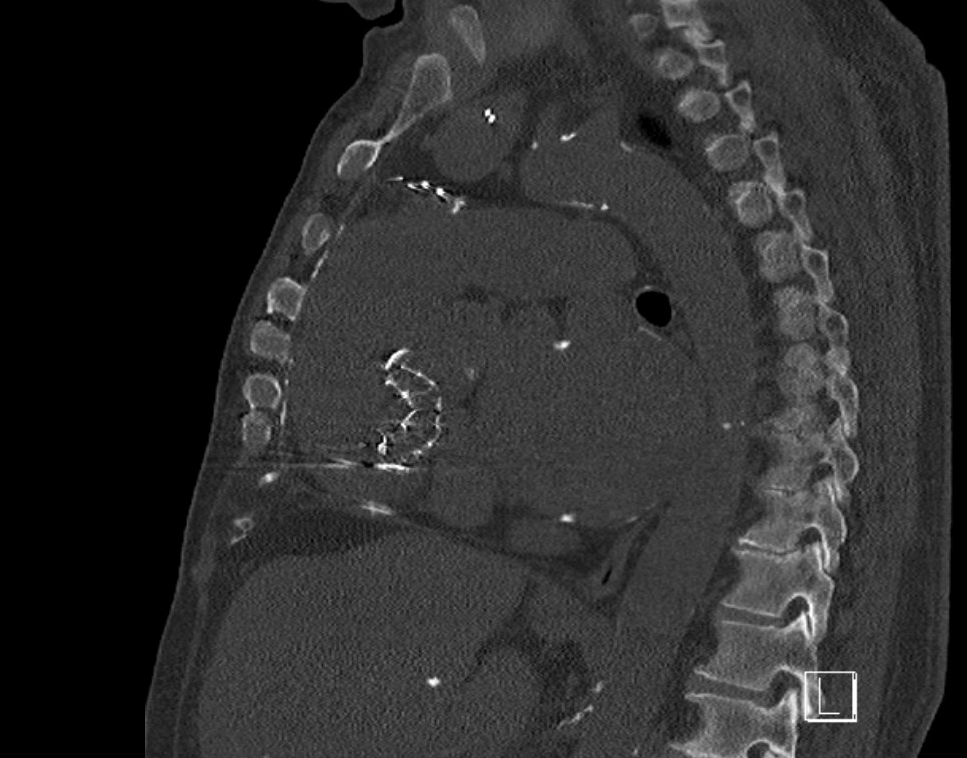

NI DCM. EF 25%. #ECG #EPeeps #CardioTwitter @AdolfoFontenla @jvillacastin @ALFIEEP1 @EF_Cardiaca @Ed_Gerst @Arritmias_HRC @FellowEP @syamkumarmd @DrRoderickTung @ArritmiasHUSC